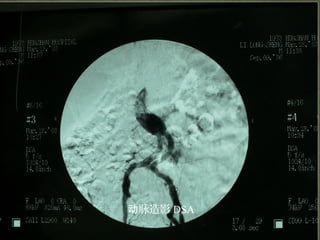

脉造影动 DSA

BUS,TCD : Convenientand easy to repeat CTA: Accurate and important tool for screening CTP : Assess cerebral ischemia and vascular reserve MRDWI/PWI: Assess indications for thrombolysis MRA: TOF/PC MRA , 3D-CEMRA DSA: Gold Standard

DSA:Gold Standard NASCET Standard*:(1- A/B)×100% ECST Standard:(1 - A/C)×100% Mild Moderate Severe NASCET < 50% 50-69% 70-99%